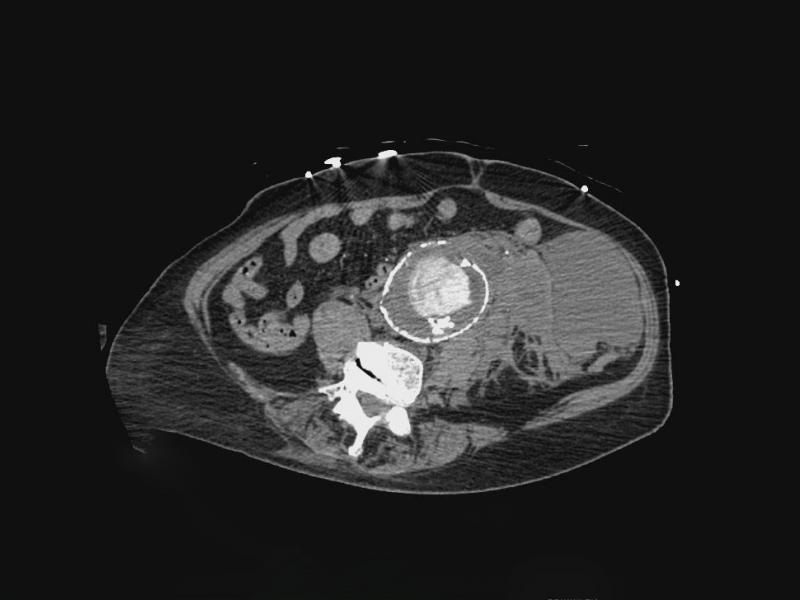

An 81 yo female presents to the ED with abdominal pain for 3